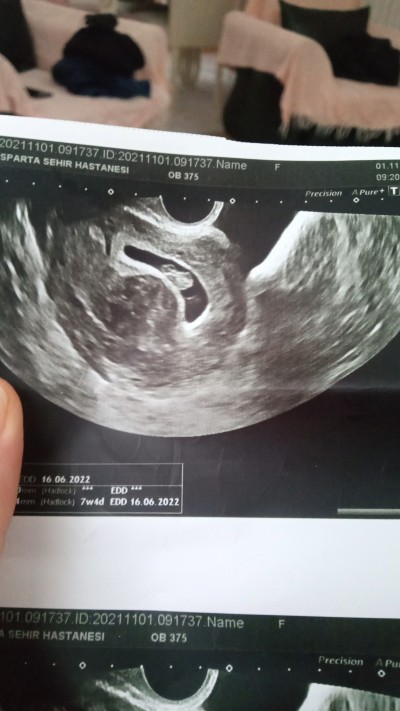

8 haftalık hamileyim..Doktor ilk başta muane ettiğinde iki kese gördü..Daha sonra kontrole

gittigimde alttan muane etti..Tek gebelik olduğunu söyledi..Ve çocuğun tam altında da 3.5cm büyüklüğünde miyom olduğunu söyledi..Baya tedirginim yakın olunca..Bir sorun yasarmiyim acaba başına gelen varmı

Gebelik haftası 8 hafta